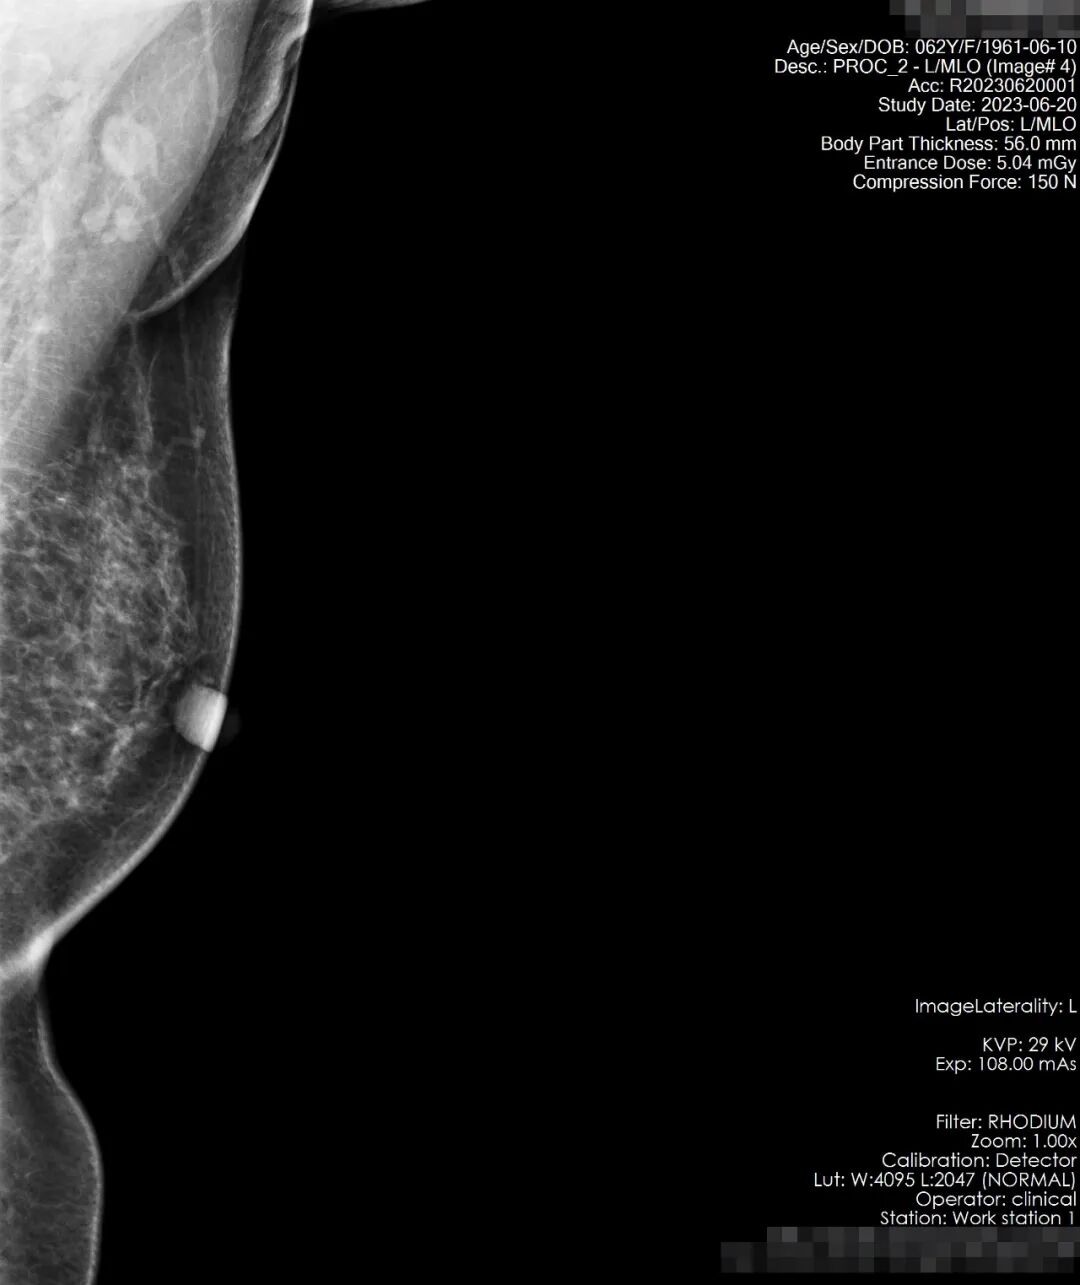

患者吴女士,58岁,在偶然一次洗澡发现自己右乳的乳头发硬并有变大的趋势,于是在网上找到了“自检”的小科普,对着镜子,开始自检,触及有疼痛感,遂即至宏宇浣江医院放射科,行乳腺钼靶检查。

检查所见:双乳腺呈散在纤维腺体型,乳腺组织丰富呈斑片状密度影,右乳内下像限见一密度增高结节影,大小约14*11mm左右,略呈分叶状,边界尚清,未见毛刺及成簇细小钙化。左乳未见明显异常,双侧腋下小淋巴结显示。双乳皮肤光整,皮下组织结构清晰,双乳头无殊。

结果显示:右乳内下像限结节,建议穿刺活检,(BI-RADS-Ⅳb类)。双侧腋下小淋巴结显示。

患者于8月2日至杭州邵逸夫医院进行全麻手术,术后病理结果为乳腺浸润性癌I期<早期>。